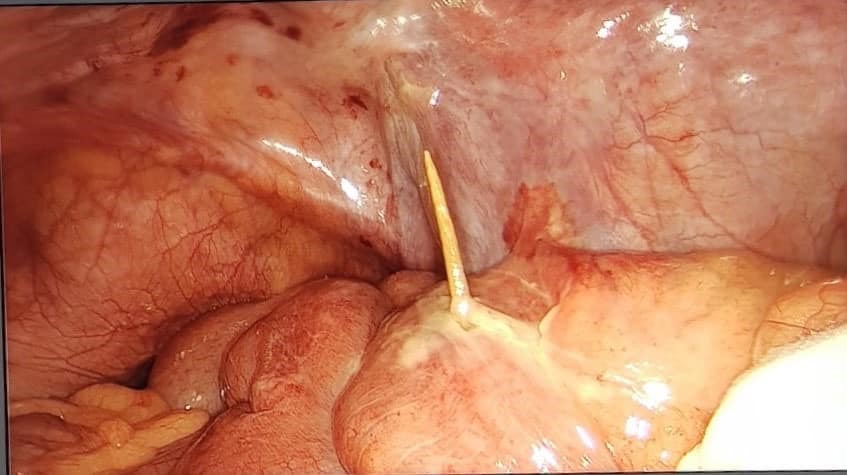

08/09/2020 21:32Nuốt phải tăm, người đàn ông bị đâm thủng ruột

Bệnh nhân có biểu hiện đau bụng nhiều, bụng chướng... được chẩn đoán viêm phúc mạc, thủng ruột non do nuốt phải tăm.

Ngày 1/9, Bệnh viện Hữu nghị Việt Đức tiếp nhận bệnh nhân H.V.H., 65 tuổi, Ứng Hòa, Hà Nội trong tình trạng tỉnh, có hội chứng nhiễm trùng, bụng chướng, đau nhiều ở bụng bên phải.

Người bệnh không có tiền sử bệnh đặc biệt. Một ngày trước khi vào viện, ông H cảm thấy đau bụng nhiều. Các bác sĩ đã thăm khám người bệnh và thực hiện các xét nghiệm thăm dò, phát hiện dị vật cản quang vùng bụng phải xuyên qua thành ruột kèm theo dịch tự do vùng bụng bên phải. Bệnh nhân được chẩn đoán viêm phúc mạc do thủng ruột non do dị vật và được tiến hành mổ cấp cứu ngay trong đêm.

Bác sĩ Tào Minh Châu, Khoa Phẫu thuật Cấp cứu Tiêu hóa, Bệnh viện Hữu nghị Việt Đức cho biết: Bệnh nhân H đã được các bác sĩ tiến hành phẫu thuật kịp thời bằng phương pháp phẫu thuật nội soi ổ bụng, kiểm tra ổ bụng thấy dị vật que tăm đâm thủng ruột non một phần nằm trong lòng ruột và một phần ở ổ bụng. Các bác sĩ đã tiến hành lấy bỏ dị vật, khâu lại lỗ thủng ruột non bằng phương pháp nội soi, rửa sạch bụng và đặt hệ thống dẫn lưu ổ bụng sau mổ.

Ca phẫu thuật trong 1 tiếng đã kết thúc thành công tốt đẹp. Sau mổ 1 ngày, người bệnh hết sốt, bụng đỡ chướng, đã trung tiện được. Sau mổ 5 ngày, người bệnh không còn tình trạng nhiễm trùng, ăn uống bình thường, chuẩn bị được ra viện.

Bác sĩ Châu cho biết thêm: trường hợp của bệnh nhân H nếu để muộn hơn dịch tiêu hóa sẽ chảy lan rộng trong ổ bụng dẫn đến viêm phúc mạc toàn thể và gây nguy hiểm đến tính mạng.

Bác sĩ khuyến cáo thói quen ngậm tăm sau ăn của nhiều người rất nguy hiểm. Mọi người có thể vô tình nuốt phải, dị vật đi vào ống tiêu hóa. Tăm tre không bị men tiêu hoá phân hủy nên sẽ di chuyển trong suốt chiều dài của lòng ruột, dễ gây nên nhiều biến chứng, nặng nhất gây thủng ống tiêu hoá và viêm phúc mạc toàn thể, ảnh hưởng đến tính mạng hoặc để lại nhiều di chứng.

Người dân nên vứt tăm đi ngay sau khi sử dụng, không ngậm trong miệng, nếu vô tình làm rơi vãi lúc trong nhà có trẻ nhỏ gây nguy hiểm hoặc bất cẩn khi nói chuyện, ngủ sẽ vô tình nuốt phải tăm....